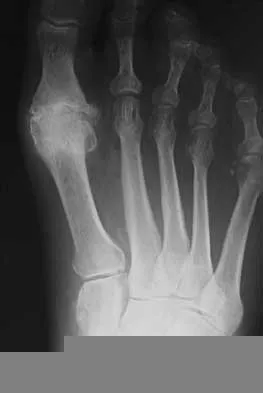

Figures 20a and 20b show the AP and lateral radiographs of a 62-year-old man who has had hip pain for the past 3 weeks. Figure 20c shows a CT scan of the abdomen and pelvis. A needle biopsy specimen is shown in Figure 20d. Preoperative management should include which of the following?

Explanation

The histology shows findings consistent with metastatic renal cell carcinoma. Renal cell carcinoma metastases are extremely vascular. Preoperative embolization helps minimize the amount of blood loss during curettage of these lesions. Chatziioannou AN, Johnson ME, Pneumaticos SG, et al: Preoperative embolization of bone metastases from renal cell carcinoma. Eur Radiol 2000;10:593-596.